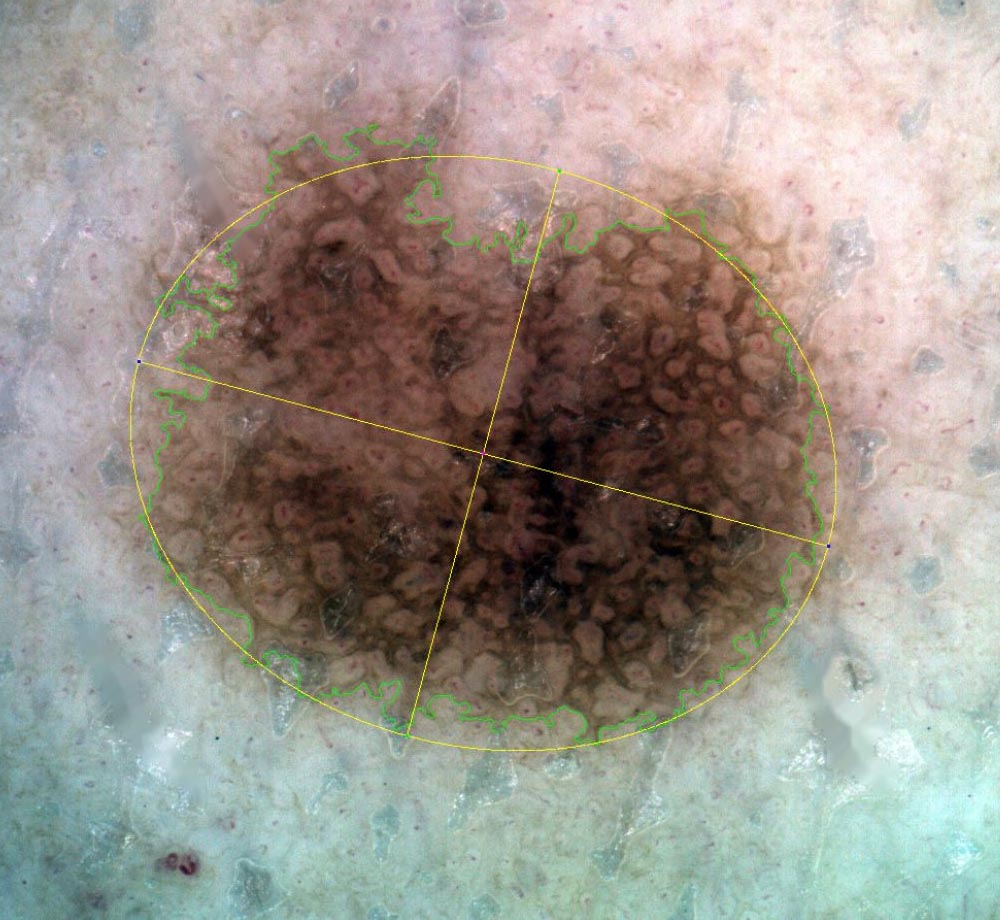

Segmentazione

La funzione di segmentazione determina il bordo della lesione i,dentificato da una curva di Jordan che separa l’area della lesione dallo sfondo.

La segmentazione manuale o automatica a seconda delle esigenze del clinico, segna il confine della lesione cutanea in tempo reale, rilevando il contorno della lesione, il suo centro, il suo orientamento e l’ellisse che si approssima all’intero neo.

Analisi

La funzione Segmentazione attiva l’analisi ABCDE su un’immagine di una lesione cutanea.

L’analisi ABCDE di IRSkin fornisce al medico informazioni quantitative riguardanti la morfologia e le caratteristiche pigmentarie della lesione cutanea.

Le funzioni di analisi ABCD, insieme alla possibilità di analizzare l’evoluzione di una lesione mediante la Body Map, forniscono informazioni quantitative e qualitative che possono aiutare il medico a migliorare la sua analisi ABCDE standard. Apparirà sullo schermo la schermata di analisi ABCD, insieme a i seguenti parametri numerici:

ASIMMETRIA:

Simmetria rispetto l’asse maggiore (percentuale di simmetria della pelle segmentata rispetto al suo asse maggiore di inerzia)

Simmetria rispetto l’asse minore (percentuale di simmetria della pelle segmentata rispetto al suo asse minore di inerzia)

Simmetria rispetto al centro (percentuale di simmetria della pelle segmentata rispetto al suo baricentro)

Simmetria media (media delle tre simmetrie precedenti)PARAMETRI DEL CONTORNO

Fattore di forma (quantità numerica che misura la complessità del contorno di una forma rispetto alla sua area: è proporzionale al rapporto tra l’Area della lesione cutanea e il quadrato del suo Perimetro. I piccoli valori del Fattore di forma indicano che la lesione ha un confine articolato)

Circolarità di Haralick (quantità statistica che misura la somiglianza di una forma con un cerchio) I grandi valori della circolarità dell’Haralick indicano che la lesione ha un’elevata circolarità

Ellitticità (quantità numerica che misura la somiglianza di una forma con la sua ellisse inerziale) I grandi valori di ellitticità indicano che la lesione è simile alla sua ellisse inerziale)

Eccentricità (quantità numerica che misura il rapporto tra gli assi inerziali di una forma: valori elevati di Eccentricità indicano una estesa lesione cutanea)COLORE:

Colore dominante (grafico che indica la distribuzione dei colori prevalenti della lesione cutanea)

Visualizzazione zone di colore(dei colori prevalenti della lesione cutanea e dei suoi assi inerziali)

Colore Entropia (quantità statistica, definita dal Team IRSkin, che misura le variazioni di colore della lesione cutanea tra i suoi quattro quarti)PARAMETRI DIMENSIONALI (espressi in millimetri):

Diametro (distanza massima tra due punti di una lesione cutanea)

Area (misura dell’area coperta dalla lesione cutanea)

Perimetro (misura della lunghezza del confine della lesione cutanea)

Lunghezzaì(misura della lunghezza dell’asse maggiore della lesione cutanea)

Altezza (misura della lunghezza dell’asse minore della lesione cutanea)